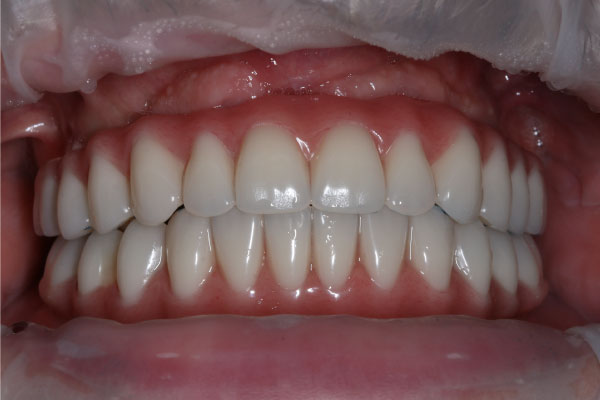

Имплантация зубов: фото «До» и «После»

Фото ДО

Фото ПОСЛЕ

Наведите для просмотра

All-on-4